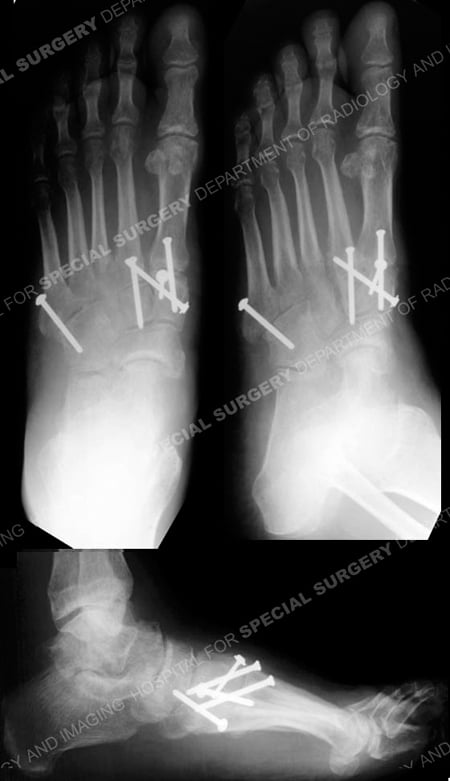

Anteroposterior, oblique, and lateral radiographs at 3 months illustrating a healing Lisfranc fracture-dislocation.